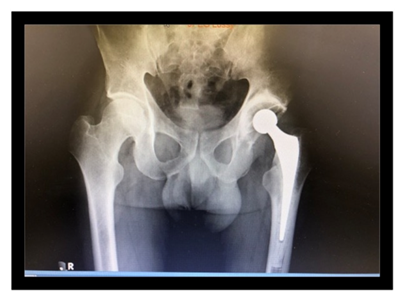

Material y Métodos: Reporte del caso

Presentamos el caso de un paciente de 49 años, trabajador de la construcción, sin patología previas, procedente del interior del Uruguay, quien otorgó su consentimiento verbal y escrito para la publicación de su caso. Sufre un accidente automovilístico en febrero del 2019, viajando como acompañante en asiento trasero sin cinturón de seguridad, sufriendo lesión de cadera izquierda al impactar la rodilla con el respaldo del asiento delantero. De la valoración inicial al momento de la asistencia en el lugar, no presenta lesión de cráneo, raquis, tórax ni abdomen y se constata miembro inferior derecho acortado, tumefacción en raíz de muslo y parestesias de miembro inferior derecho en territorio del nervio ciático poplíteo externo. Los pulsos distales estaban presentes y no presentaba otras lesiones del sistema músculo esquelético ni compromiso vascular. No se realizó ninguna maniobra sobre la cadera del paciente, ni en el lugar del accidente, ni en el centro asistencial. En la radiografía de frente, absolutamente atípica, se diagnostica luxación de cadera izquierda con fractura de cuello femoral, y el fragmento epifisario en dirección inversa (cuello hacia el acetábulo, y cabeza hacia el macizo trocantérico) (figura 1). La tomografía confirma luxación posterior del fragmento con la disposición antes mencionada, sin lesión ósea de la cabeza femoral, ni del acetábulo (figura 2, 3, 4, 5).

Figura 1: Radiografía inicial excepcional: Epífisis de posición invertida

La estabilización inicial del paciente se realizó en un centro asistencial cercano al lugar del accidente, siendo derivado a un centro de tercer nivel con 12 horas de evolución. Se realiza una valoración imagenológica la cual confirma el diagnóstico (figura 1). La tomografía confirma la asociación lesional y descarta otras lesiones concomitantes. Antes del tratamiento definitivo no se utilizaron otros métodos diagnósticos para descartar lesiones vasculares o confirmar la lesión neurológica del paciente. Dada la edad del paciente, el tiempo de evolución, el desplazamiento de la lesión ósea asociada a la luxación con alta probabilidad de osteonecrosis, se decidió realizar una artroplastia total de cadera. La cirugía se llevó a cabo 16 días luego del accidente. Por vía anteolateral trans-glúteo medio, al abrir la fascia, la cabeza femoral estaba subcutánea en el sector posterolateral (figura 6). Se buscó el nervio ciático que estaba sano. Se utilizó una prótesis cementada, con tallo cónico pulido, con cabeza 28 Metal-Polietileno.